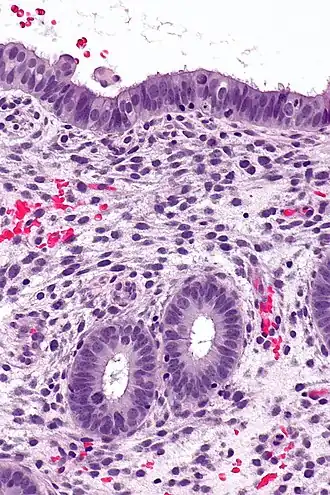

![]() Endometrium in the proliferative phase | |

The endometrium consists of a single layer of columnar epithelium plus the stroma on which it rests. The stroma is a layer of connective tissue that varies in thickness according to hormonal influences. In the uterus, simple tubular glands reach from the endometrial surface through to the base of the stroma, which also carries a rich blood supply provided by the spiral arteries. In women of reproductive age, two layers of endometrium can be distinguished. These two layers occur only in the endometrium lining the cavity of the uterus, and not in the lining of the fallopian tubes where a potentially life-threatening ectopic pregnancy may occur nearby.[4][5]

- The functional layer is adjacent to the uterine cavity. This layer is built up after the end of menstruation during the first part of the previous menstrual cycle. Proliferation is induced by estrogen (follicular phase of menstrual cycle), and later changes in this layer are engendered by progesterone from the corpus luteum (luteal phase). It is adapted to provide an optimum environment for the implantation and growth of the embryo. This layer is completely shed during menstruation.

- The basal layer, adjacent to the myometrium and below the functional layer, is not shed at any time during the menstrual cycle. It contains stem cells that regenerate the functional layer,[1] which develops on top of it.

It is possible to identify the phase of the menstrual cycle by reference to either the ovarian cycle or the uterine cycle by observing microscopic differences at each phase—for example in the ovarian cycle:

| Phase | Days | Thickness | Epithelium |

|---|---|---|---|

| Menstrual phase | 1–5 | Thin | Absent |

| Follicular phase | 5–14 | Intermediate | Columnar |

| Luteal phase | 15–27 | Thick | Columnar. Also visible are arcuate vessels of uterus |

| Ischemic phase | 27–28 | Columnar. Also visible are arcuate vessels of uterus |